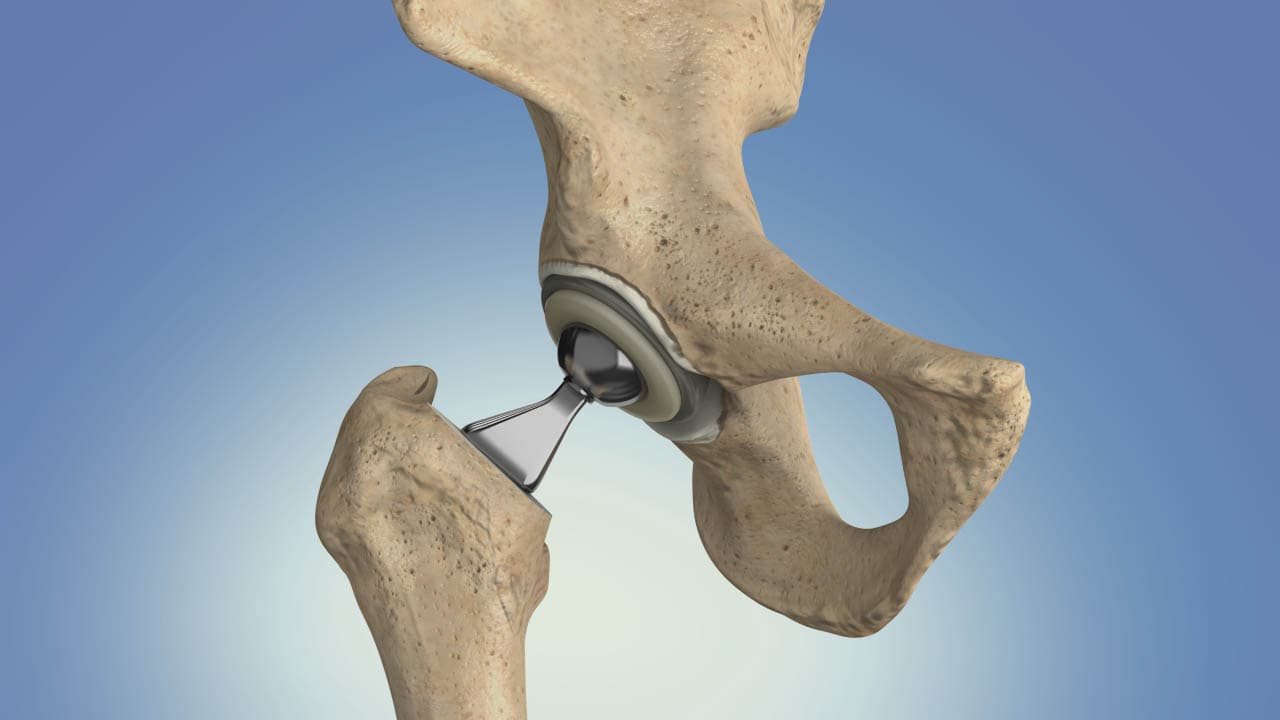

A hip replacement is a surgical procedure in which the damaged parts of the hip joint are removed and replaced with a prosthesis designed to replicate the ball‑and‑socket mechanics of a healthy hip. In a total hip arthroplasty the surgeon replaces both the femoral head (the ball) and the acetabular socket; a hemiarthroplasty replaces only the femoral head in select fracture cases. Implants are typically made from combinations of metal, ceramic, and high‑density polyethylene to provide durable, low‑friction motion. The operation is indicated when hip pain and stiffness significantly limit daily activities and conservative measures—such as medications, physical therapy, weight management, and injections—no longer provide adequate relief. Surgeons choose an approach and fixation method (cemented, uncemented, or hybrid) based on patient age, bone quality, and activity level; uncemented components rely on bone ingrowth into a porous surface, while cemented components are fixed with bone cement. The procedure usually takes one to two hours under regional or general anesthesia, and most patients begin mobilizing with physical therapy within 24 hours. Modern hip replacements can last many years, often 15 years or more, but implant longevity depends on activity, implant type, and surgical technique.

A total hip replacement (total hip arthroplasty) replaces both the femoral head (ball) and the acetabular socket with prosthetic components and is the most common option for end‑stage arthritis because it reliably relieves pain and restores function; implants may be cemented, uncemented, or hybrid depending on bone quality and surgeon preference.